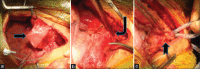

Pelvic fracture with urethral injury in girls is an uncommon entity that is usually associated with concomitant vaginal lacerations. Management options vary from immediate exploration and urethral anastomosis to delayed urethroplasty. We report our experience of managing a 10-year old girl presenting 6 months after a pelvic fracture with urethrovaginal injury and a completely obliterated urethral meatus managed successfully with a single-stage bladder tube repair.